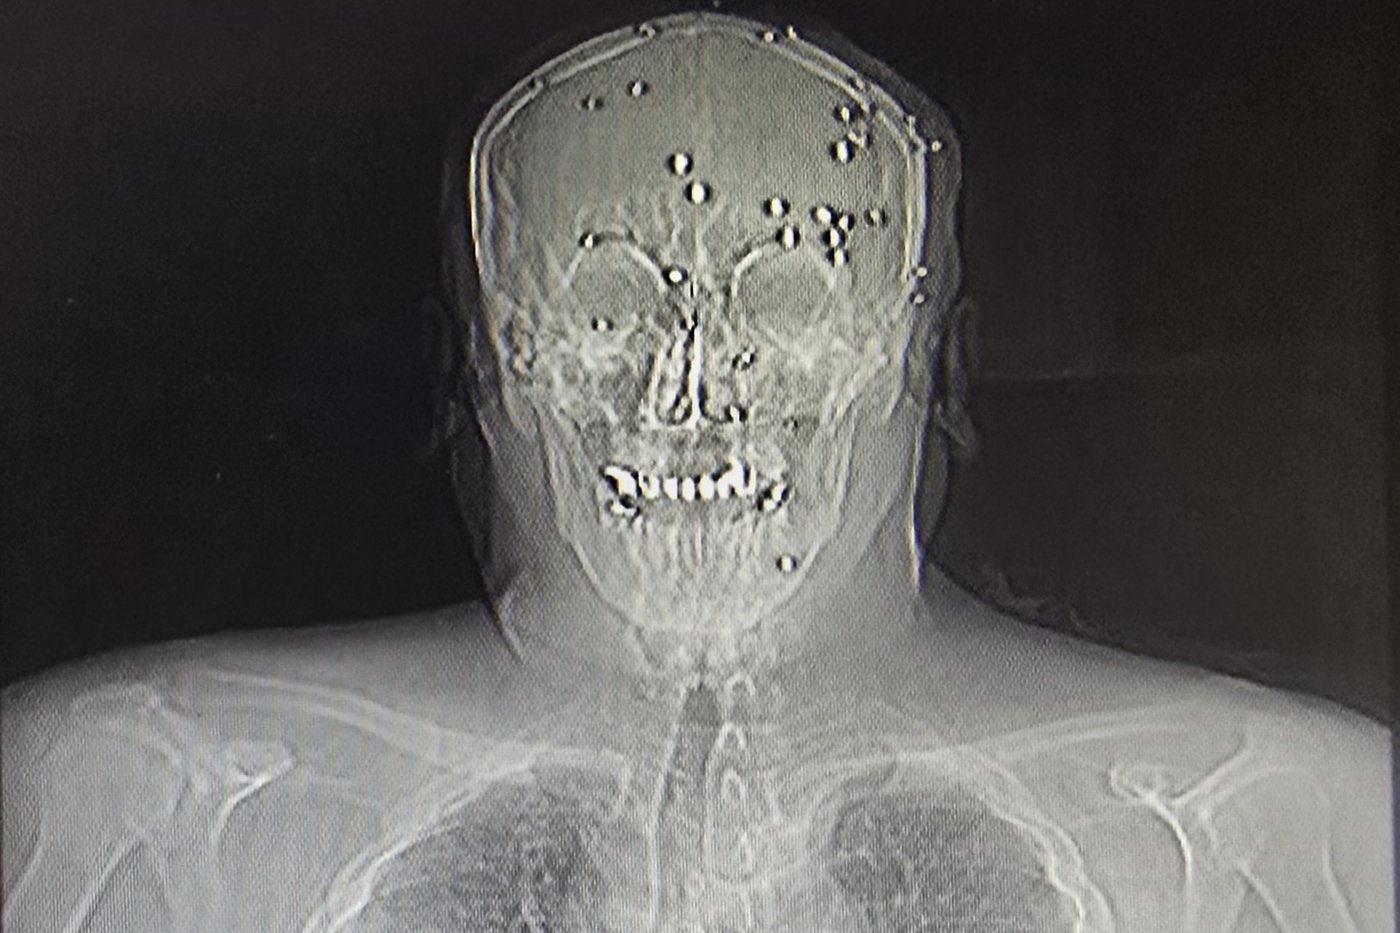

At one point, security agents brought in the body of a dead man with his hands shackled in front of his body. He had pellet shots to his abdomen and chest and a clear bullet wound to the head, he said.

Amnesty International has received credible reports that targeted, close-range shootings of protesters took place, and “at a far greater scale” than in past crackdowns on protests, said the group’s Iran researcher Raha Bahereini. Two videos verified by AP show the bodies of protesters with close-range shots and medical equipment connected to their bodies.

One woman, in her 30s, had been hit by bird shot at close range, destroying the roof of her mouth and the area around her nose and below her eyes, the surgeon recalled.

A young man in his 20s had been shot with live ammunition in his elbow, shattering it. The surgeon sutured the wounds but knew the arm would have to be amputated.

A family of four — a mother, father and their 8- and 10-year-old children — were all riddled with pellets, the surgeon said. The older boy had dozens of pellets in his face, but amazingly none hit his eyes.

On the morning of Jan. 9, the phone lines started working again, and the surgeon reached out to doctors he trusted to refer patients to them. First he had to make sure to remove all bullets and pellets from their bodies so they wouldn’t be detained at the hospital. He wrote referral letters saying the patients had been in car accidents.